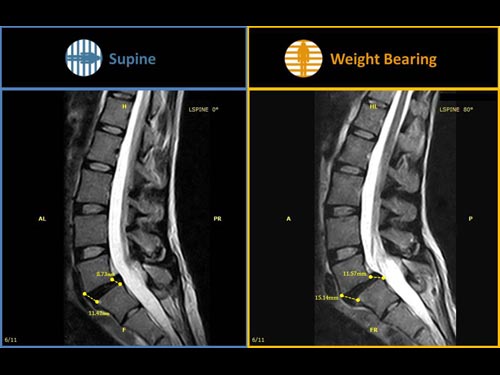

Nová končetinová magnetická rezonance G-scan Brio od společnosti Esaote je tomografický systém MRI, který umožňuje studium všech kloubů i páteře, ať už v klinostatické (vleže) nebo ortostatické (vážící) poloze, protože magnet i pacient se mohou otáčet od 0 do 90 stupňů. Díky inovativnímu designu G-scan mohou být pacienti Brio skenováni v poloze nesoucí váhu, aby se usnadnila diagnostika MSK u těch patologií, které se mohou měnit v důsledku držení těla a polohy, jako jsou bolesti dolní části zad.

• Váhové ložisko: poloha pacienta se stává nedílnou součástí výsledku vyšetření

• Další diagnostické schopnosti: jelikož gravitační síla generuje bio-mechanické změny v anatomii, MR zobrazení v přirozené poloze ve stoje vám umožňuje dosáhnout důležitých dalších informací ve srovnání s tradičními MRI